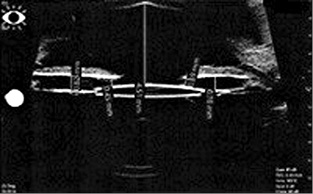

При контрольном осмотре 24.04.2016 жалоб пациентка не предъявляла. По данным ультразвуковой биомикроскопии, зона патологического контакта пигментного листка радужной оболочки с передней поверхностью хрусталика и цинновыми связками стала меньше, но сохранялась (рис. 3, 4). Рекомендовано наблюдение в динамике.

Рис. 3. Правый глаз, ультразвуковая биомикроскопия после лазерной периферической иридотомии

Рис. 4. Левый глаз, ультразвуковая биомикроскопия после лазерной периферической иридотомии